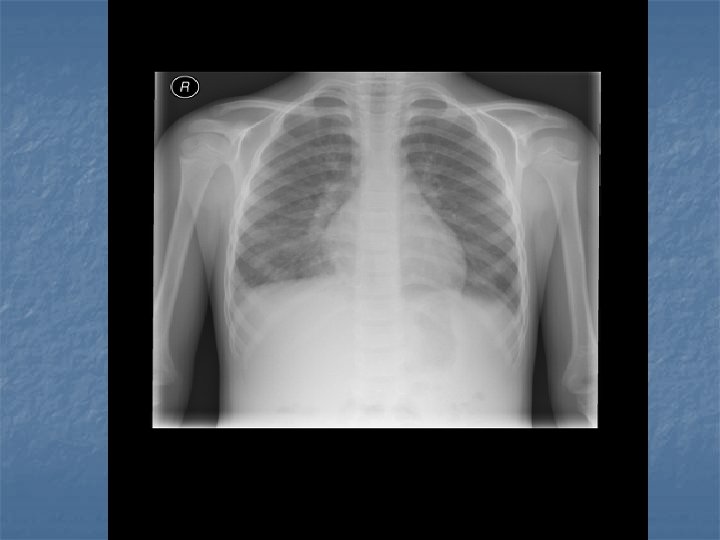

CXR Findings VIRAL n Peribronchial thickening n Diffuse interstitial infiltrates n Hyperinflation BACTERIAL n Subsegmental, segmental or lobar infiltrates n Air bronchograms n Round pneumonia in early S. pneumo n n M. pneumo diffuse infiltrates out of proportion to clinical findings (or bronchopneumonia infiltrates in lower lobes) Bilateral reticulonodular interstitial infitrates

n n n 50% bacterial pneumonia will have lobar infiltrate Can also see alveolar infiltrates Round pneumonia seen with S. pneumo

CXR Summary n In combination with physical exam, do a CXR when: Questionable dx n Admitting pt n <3 y with fever >39 C and WBC >15 n Complicated pneumonia suspected n

Investigations Pediatric CAP n n CXR gold standard for all pneumonias CBC, diff, blood cultures n n n Usu WBC consists of polymorphs Can get leukocytosis with adeno, influenze or Mycoplasma Viral infections can cause leukopenia OR it is a sign of overwhelming bacterial infection Gram stain/culture if older child >2 y. o. consider Mycoplasma Ig. M ELISA(cold agglutinins are of no help) RSV testing not routinely recommended